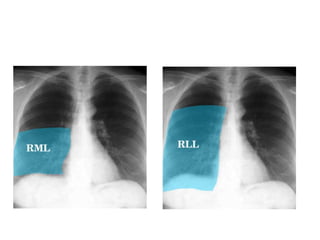

1- Determine location :

Loss of heart borders or of the contour of the diaphragm

E.g. : Right middle lobe consolidation blurs the heart

border

The lingula blurs the left side border of the heart

Right middle lobe consolidation

Left lower lobe consolidation

Figure 7: Right middle lobe pneumonia

Right middle lobe pneumonia